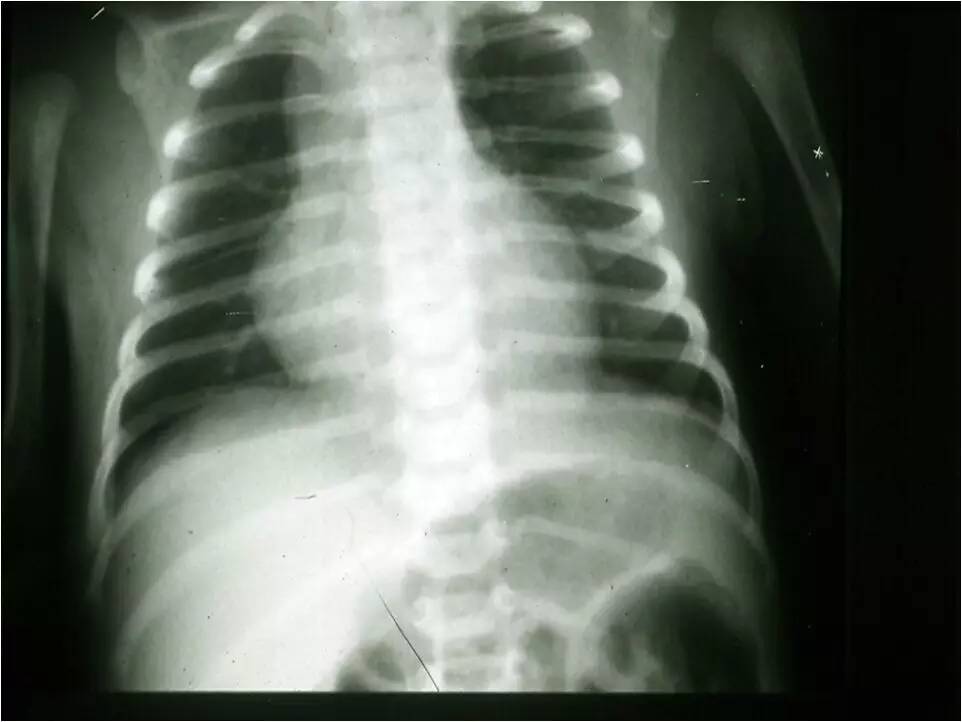

MAS影像学表现

↑A-P 直径

临床和研究结果临床特征肺功能影像学图片